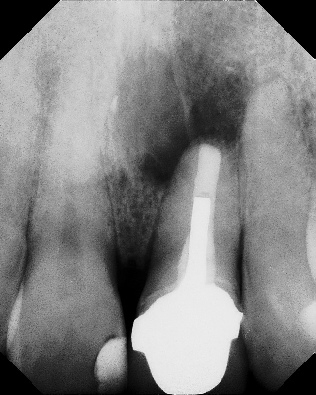

COMPLICATED ANATOMY LARGE LESIONS CALCIFIED CANALS PERFORATION / RESORPTION SEPARATED INSTRUMENTS SURGICAL CASES RETREATMENT / pOST REMOVAL OPEN APICES ACCESS THRU CROWNS Root Canal Case Portfolio

Apicoectomy - Surgical Root Canal Pre-op (post trauma) Coronal segments obturated Apical segments surgically removed 3 years